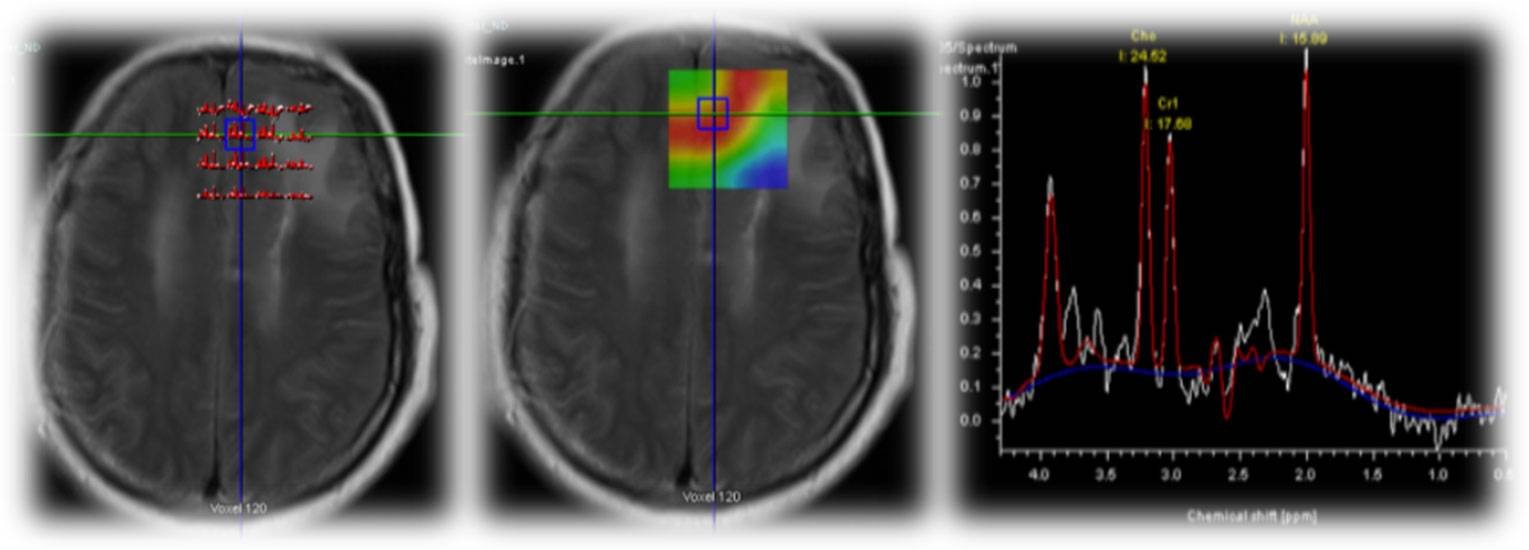

A 5-year-old male child presented with complaints of recurrent generalized tonic–clonic seizures and right-sided weakness ,predominantly involving the lower limb along with anger outbursts and abnormal behaviour.